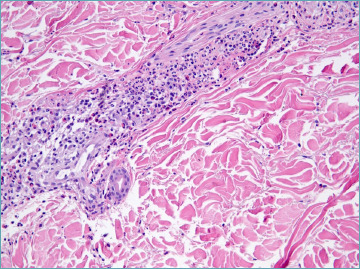

The mechanisms underlying the onset and progression of vasculitis remain poorly understood. This condition is characterized by damage to the vascular wall, recruitment of inflammatory cells, and subsequent structural remodeling, which are hallmarks of vasculitis. The histopathological classification of vasculitis relies on the size of the affected vessel and the predominant type of inflammatory cell involved - neutrophils in acute cases, lymphocytes in chronic conditions, and histiocytes in granulomatous forms. Pathological changes progress in every context, and a single vasculitic pattern can be associated with various systemic conditions. Conversely, a single causative agent may lead to multiple distinct clinical and pathological manifestations of vasculitis. Moreover, many cases of vasculitis have no identifiable cause. A foundational understanding of the normal structure of the cutaneous vascular network is crucial. Similarly, identifying the cellular and molecular participants and their roles in forming the "dermal microvascular unit" is propedeutical.

This review aims to elucidate the complex mechanisms involved in the initiation and progression of vasculitis, offering a comprehensive overview of its histopathological classification, underlying causes, and the significant role of the cutaneous vascular network and cellular dynamics. By integrating the latest insights from studies on NETosis and the implications of lymphocytic infiltration in autoimmune diseases, we seek to bridge gaps in current knowledge and highlight areas for future research. Our discussion extends to the clinical implications of vasculitis, emphasizing the importance of identifying etiological agents and understanding the diverse histopathological manifestations to improve diagnostic accuracy and treatment outcomes.